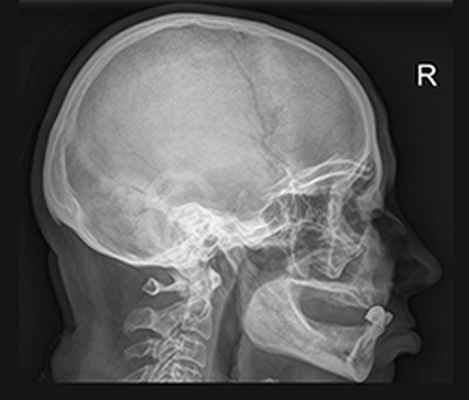

Рентгенография черепа

Рентген черепа – это метод лучевой диагностики, который применяется для исследования костей свода и основания черепа, костей лицевого скелета и головного мозга. Рентгенологическое исследование черепа помогает поставить диагноз, решить вопрос с выбором тактики лечения и проконтролировать динамику лечебного воздействия. Рентген черепа обычно выполняется в положении лежа или сидя с фиксированной с помощью специальных приспособлений головой. Врач может назначить исследование в одной или нескольких проекциях: правой боковой, левой боковой, переднезадней, заднепередней, аксиальной, полуаксиальной, прицельной. При этом потребуется снять все металлические аксессуары с шеи и головы.

Диагностика заболеваний черепа может включать различные виды рентгенографии, которые назначаются в зависимости от клинических проявлений и истории заболевания:

- обзорная рентгенография черепа;

- прицельная рентгенография:

- рентгенография нижней челюсти;

- рентгенография костей носа;

- рентгенография глазниц;

- рентгенография турецкого седла;

- рентгенография скуловой кости;

- рентгенография сосцевидных отростков височной кости;

- рентгенография височно-нижнечелюстных суставов.

Обзорная рентгенография черепа проводится в обязательном порядке при травмах головы, с целью обнаружения переломов свода и основания черепа, смещения костных отломков. В случае высокой плотности костной ткани переломы могут быть не распознаны, поэтому рентгенологический метод уступает по точности и достоверности компьютерной томографии, но является более простым и быстрым способом диагностики.

Помимо переломов обзорный рентген черепа позволяет обнаружить:

· врожденные аномалии развития;

· признаки остеомиелита (очаги кальцификации костей);

· признаки хронической субдуральной гематомы (очаги внутричерепной кальцификации);

· обызвествленные опухоли головного мозга (менингиомы, олигодендромы);

· обменные нарушения (характерные для болезни Педжета и акромегалии);

· эндокраниоз;

· заболевания придаточных пазух носа;

· признаки внутричерепной гипертензии.

Рентгенография турецкого седла помогает обнаружить опухоли гипофиза (чаще всего пролактиному), остеопороз турецкого седла и особенности сосудистого рисунка, вызванные высоким внутричерепным давлением. На снимке оценивается форма, контуры и размеры турецкого седла. При увеличении его размеров, расширении входа в турецкое седло, появлении двухконтурности делают предположение о наличии опухоли гипофиза и продолжают диагностический поиск в указанном направлении.

Рентгенография височно-нижнечелюстных суставов помогает в диагностике артрозов, переломов суставного отростка, дисфункциональных синдромов. Исследование может выполняться при закрытом и максимально открытом рте.

Рентгенография сосцевидных отростков височной кости чаще всего востребована при гнойном мастоидите (воспалении сосцевидного отростка).

Рентгенография скуловой кости применяется для подробного исследования скуловой области, если имеются локальные боли, деформация.

Рентгенография глазниц назначается, в первую очередь, при черепно-мозговых травмах, так как часто отмечаются переломы в данной области, а также для обнаружения инородных тел глазниц или глазных яблок.

Рентгенография костей носа востребована при травмах, переломах носовых костей.

Рентгенография нижней челюсти чаще всего назначается при ее переломах и опухолях.